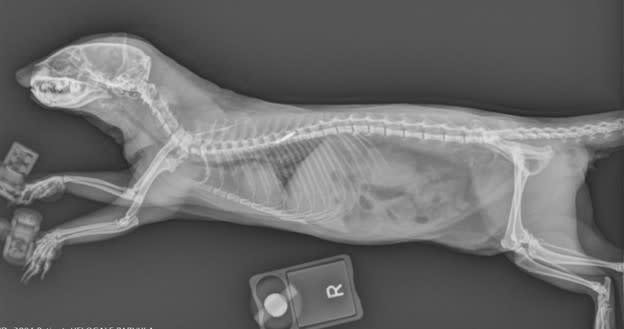

Brookfield Zoo Chicago's Radiology Consulting Service helps veterinarians worldwide give the best medical care to zoo and aquarium animals. We also develop new imaging techniques and support conservation programs.

New imaging technologies have greatly improved veterinary care for wild animals. Techniques that were once rare are now used in everyday treatment. Because veterinarians work with so many different species, staying an expert in all areas is a big challenge.

Our radiologists provide the expertise and high-quality service vets need to make accurate diagnoses and create effective treatment plans.

Traditionally, most veterinary radiology has focused on pets, leaving many zoo species less understood. We are committed to changing that.